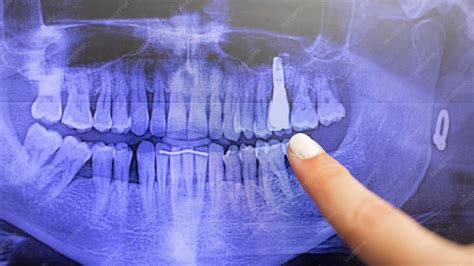

Problemas con coronas en implantes dentales

Las coronas en implantes dentales son una solución común, pero también pueden presentar problemas:

- Ajuste impreciso: Si la corona no está colocada de forma precisa, puede haber fricción y aflojamiento.

- Fallo del material de fijación: El material utilizado para fijar la corona al implante puede no unirse adecuadamente.

- Fallo en el implante: En ocasiones, el problema puede estar en el propio implante.

¿Por qué se aflojan las coronas en implantes?

Una de las causas más habituales es un exceso de presión en la zona. También puede influir el bruxismo, el fallo en el torque del tornillo o el paso del tiempo.

¿Qué hacer si se afloja una corona sobre un implante?

- Acude al dentista cuanto antes.

- Mantén una buena higiene oral.

- Acude a revisiones periódicas.

- Si tienes bruxismo, usa una férula de descarga.

- Evita usar los dientes para lo que no están hechos.

Que una corona se afloje no es algo grave, pero sí necesita atención. Es un pequeño recordatorio de que los implantes, aunque muy resistentes, también necesitan seguimiento.